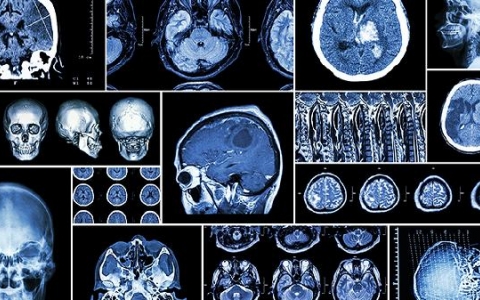

什么是脑瘤前期筛查方法有哪些

脑实质发生的原发性脑瘤和由身体其他部位转移至颅内的继发性脑瘤。腌制品、发霉食物、烧烤烟熏类食物食品添加剂、农药中毒污染的农作物。头部的肿瘤一般情况下ct和核磁共